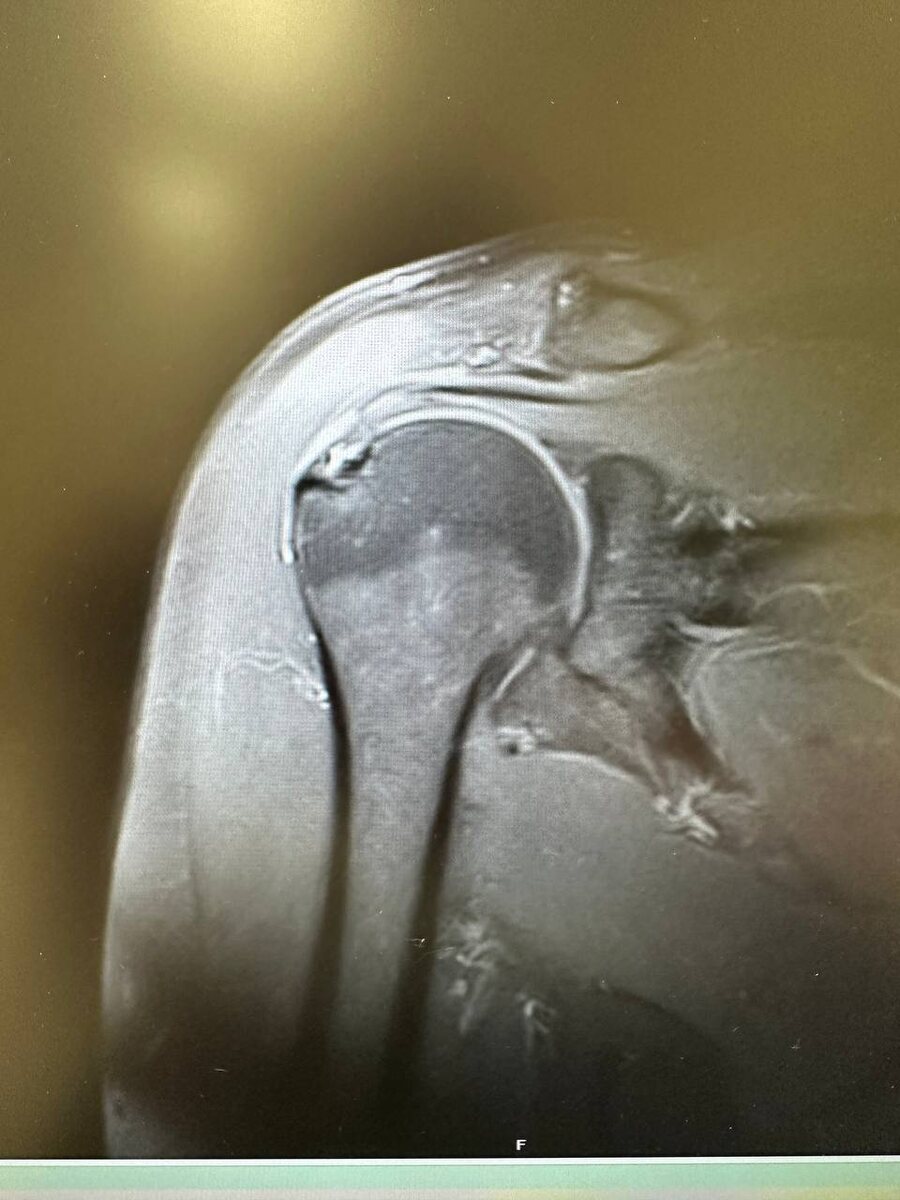

Образование головки плечевой кости. Пациент направлен к онкологу. На фото головка в норме для сравнения.

Образование головки плечевой кости. Пациент направлен к онкологу.

На фото головка в норме для сравнения.